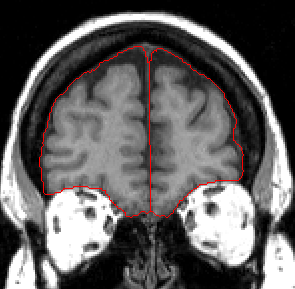

In the anterior portion of the ICC, using either the outline provided by the automation or a contour you generate, extract outlines that include all visible Cortex as well as all surrounding CSF. Draw a line to divide the ICC into left and right hemispheres and then extract each side separetely.

Take care to exclude all dura mater and sinuses.

Moving posteriorly, take care to exclude the Superior Sagittal Sinus, as it is often included by the automation.